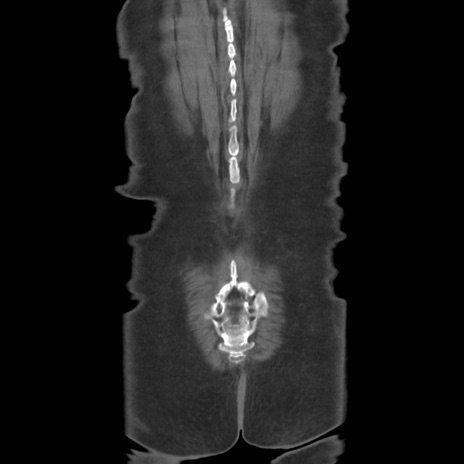

症例19(冠状断像)

【症例】80歳代女性

【主訴】下腹部痛

【現病歴】約8時間前より下腹部痛の出現あり、救急外来受診。

【既往歴】両側付属器切除

【身体所見】意識清明、下腹部正中に手術痕あり、その部位に一致して圧痛と反跳痛あり。腸蠕動音は亢進。

【データ】WBC 9300、CRP 0.15